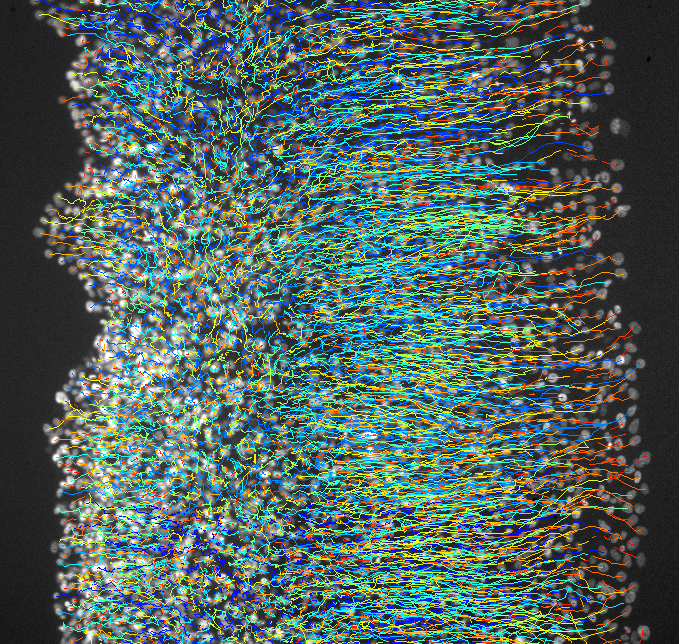

Éxito del trasplante de células alveolares para tratar la fibrosis pulmonar idiopática

16/06/2016